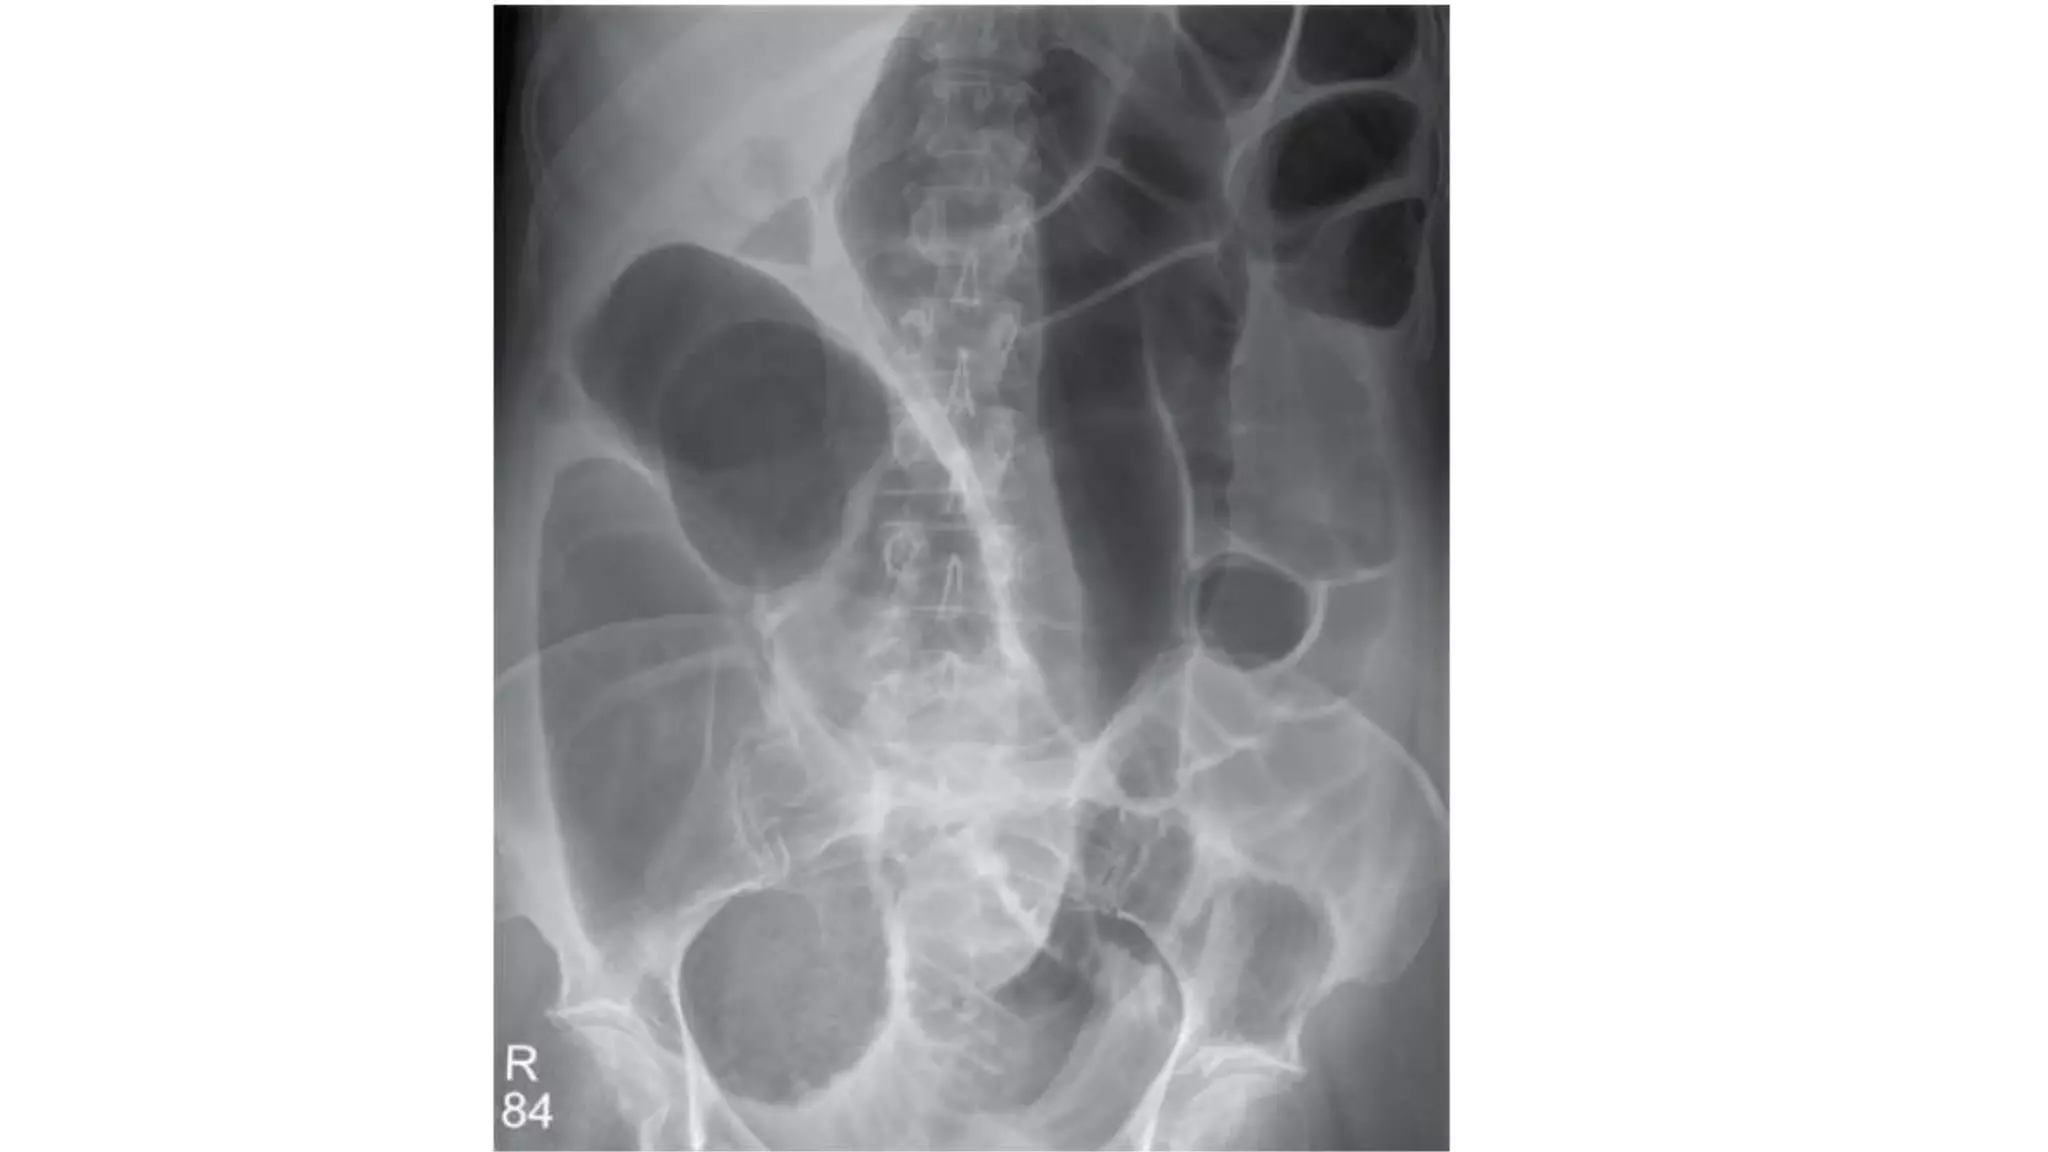

• CT scan — In patients with axial torsion of the cecum (type I or II), a

obstruction (a massively dilated cecum with associated small bowel

dilation) (image 5) or signs of colonic or small bowel ischemia (mural

thickening or mesenteric edema) [9]. In patients with a cecal bascule (type

III), CT scan shows the cecum folding upward, resulting in obstruction

without the axial twist of the mesentery (image 6).